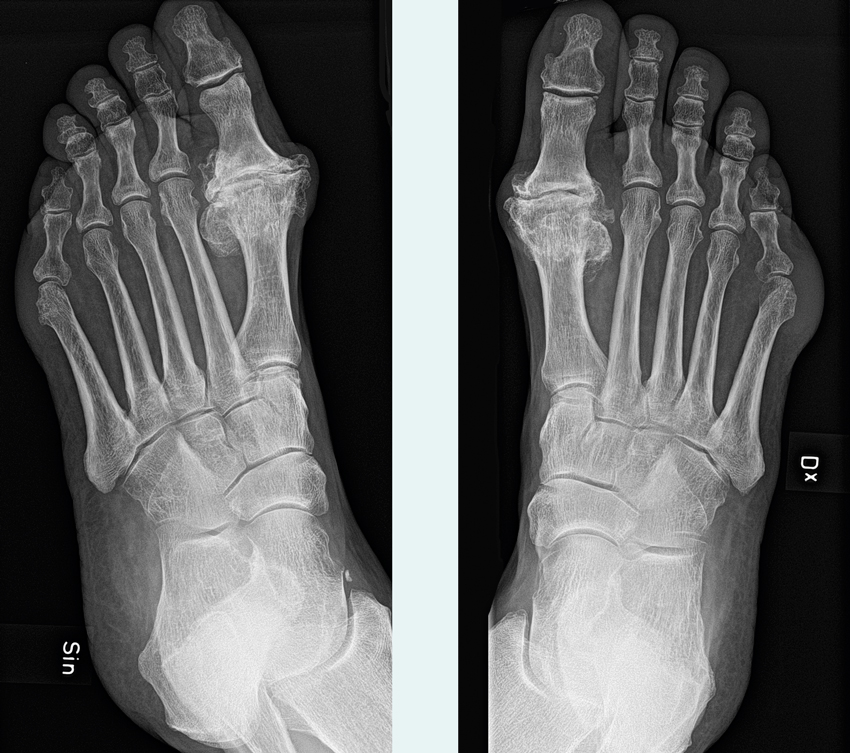

Slätröntgen med belastning av A) vänster och B) höger fot hos patient med hallux rigidus. Observera kantpålagringar på metatarsofalangealled-I på höger fot. På vänster fot ses också uttalad artrosförändring, med mer uttalade pålagringar på mediala samt dorsala ledytekanterna.

• Hallux rigidus klassificeras efter rörelseomfång, kliniska och radiologiska fynd. Ett flertal klassificeringssystem finns att använda sig av, varav Coughlins metod är den mest etablerade [28].

• Slätröntgen med belastning bör genomföras vid misstänkt hallux rigidus i standardprojektioner (frontal- och sidobild).